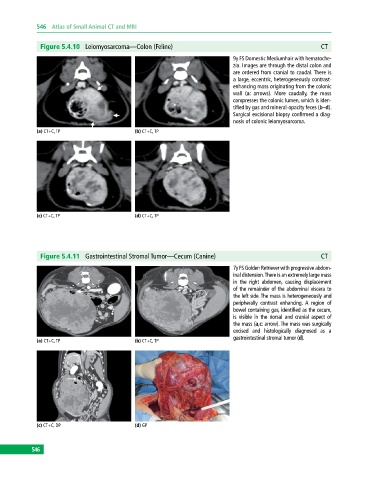

Figure 5.4.10 Leiomyosarcoma—Colon (Feline) CT

9y FS Domestic Mediumhair with hematoche-

zia. Images are through the distal colon and

are ordered from cranial to caudal. There is

a large, eccentric, heterogeneously contrast‐

enhancing mass originating from the colonic

wall (a: arrows). More caudally, the mass

compresses the colonic lumen, which is iden-

tified by gas and mineral‐opacity feces (b–d).

Surgical excisional biopsy confirmed a diag-

nosis of colonic leiomyosarcoma.

(a) CT+C, TP (b) CT+C, TP

(c) CT+C, TP (d) CT+C, TP

Figure 5.4.11 Gastrointestinal Stromal Tumor—Cecum (Canine) CT

7y FS Golden Retriever with progressive abdom-

inal distension. There is an extremely large mass

in the right abdomen, causing displacement

of the remainder of the abdominal viscera to

the left side. The mass is heterogeneously and

peripherally contrast enhancing. A region of

bowel containing gas, identified as the cecum,

is visible in the dorsal and cranial aspect of

the mass (a,c: arrow). The mass was surgically

excised and histologically diagnosed as a

gastrointestinal stromal tumor (d).

(c) CT+C, DP (d) GP